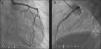

The LMCA was engaged with a 7-Fr JL4 guiding catheter (Cordis Corp., Miami Lakes, FL) (Figure 2; Video 1), and a 0.014-inch Runthrough guidewire (Terumo Medical Corp., Somerset, NJ) was passed to the distal LAD. An attempt was made to aspirate thrombotic material using an Export AP aspiration catheter (Medtronic Corp., Minneapolis), but with no success and no change in the angiographic appearance of the lesion. Neither the LCx nor its emergence from LMCA were visible, and we were unable to pass a guidewire through it. A more detailed evaluation of the lesions in several different projections showed an image suggestive of LMCA dissection (Figure 3A and B; Video 2A and B). Intravascular ultrasound was considered but was not used because of the patient's hemodynamic instability and the certainty of the diagnosis. Subsequently, the LMCA was predilated using a 3.0 mm × 15 mm balloon (TREK, Abbott Vascular, Abbott Park, IL) followed by the implantation of a drug-eluting stent (4.0 mm × 23 mm Xience Prime, Abbott Vascular, Abbott Park, IL), with a good angiographic result. After stenting, the LCx became visible and both the LAD and LCx presented no angiographic lesions (Figure 4A and B; Video 3A and B).